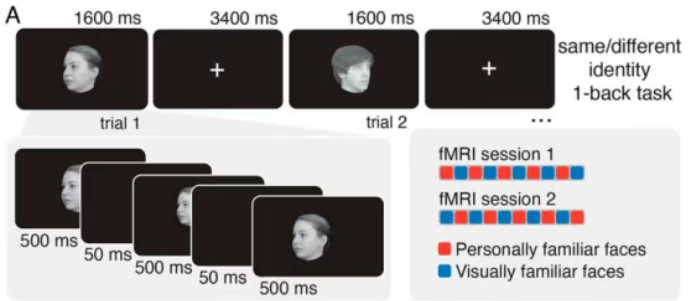

三、大脑激活:解读“思考现场”

人脑在执行特定任务(如看图片、做数学题、回忆事情)时,与该任务相关的脑区可能会被激活。 科学家们借助fMRI可获得人体大脑在这些任务状态下的图像数据,通过对比不同任务下的大脑激活图,就能知道哪些脑区参与了特定类型的思考或感知。比如,观看人脸时,与面孔识别相关的‘梭状回面孔区’可能会被激活。

大脑激活图